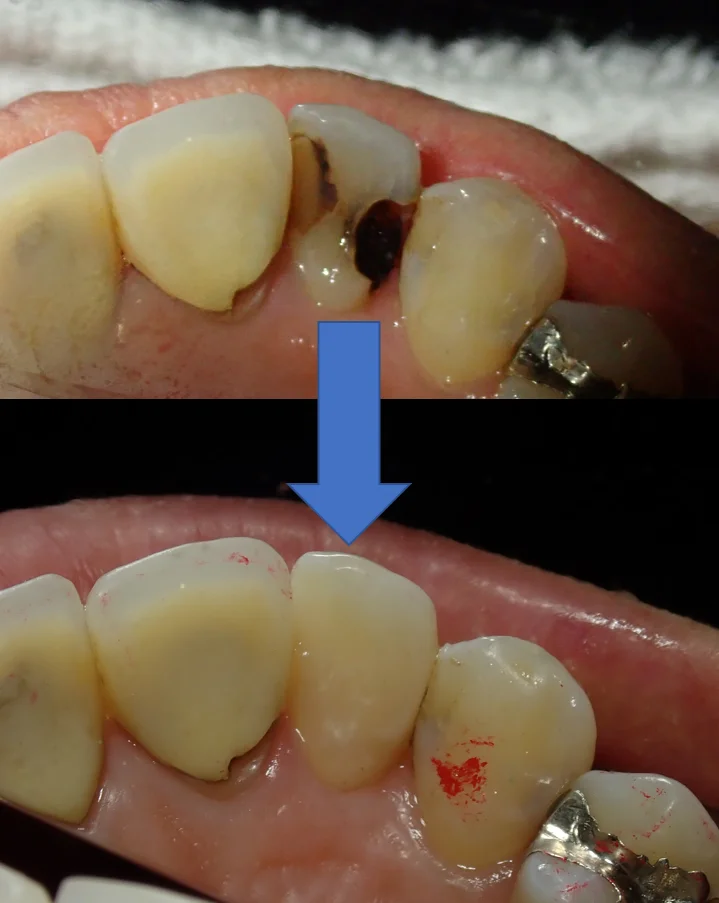

裏側から見るとこんな状態になってしまっていました。

前後の歯の間から虫歯が入り込み、歯の中央で虫歯が繋がっている状態となっています。

歯科医師によってはいきなり抜髄処置に入ってもおかしくはないほどの虫歯です。

殆どの歯医者さんではこのサイズの虫歯は、恐らく被せ物以外の選択肢を出されないかと思います。

この状態であれば、私も被せ物を勧めさせていただくことが多いですね。

ただ、今回の場合は

・そもそも下の歯と噛み合っていない

・初めて治療をする歯だったので、むやみやたらと歯を削られていなかった

・そして思った以上に歯を温存できた

という点からダイレクトボンディングによる治療が可能と判断し、本人にも説明した上で処置に入らせて頂きました。

結果としては、

裏側がこんな感じです。

本来なら全周削って被せる「クラウン」形態になるような状況でしたが、無事に歯質を多く温存できたかと思います。